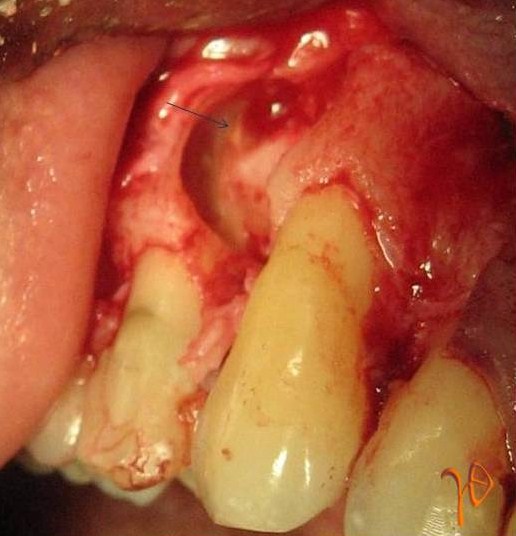

Εικ. 10 : Διεγχειρητική εικόνα του υπεράριθμου προγομφίου της Περίπτωσης-2 (βέλος).